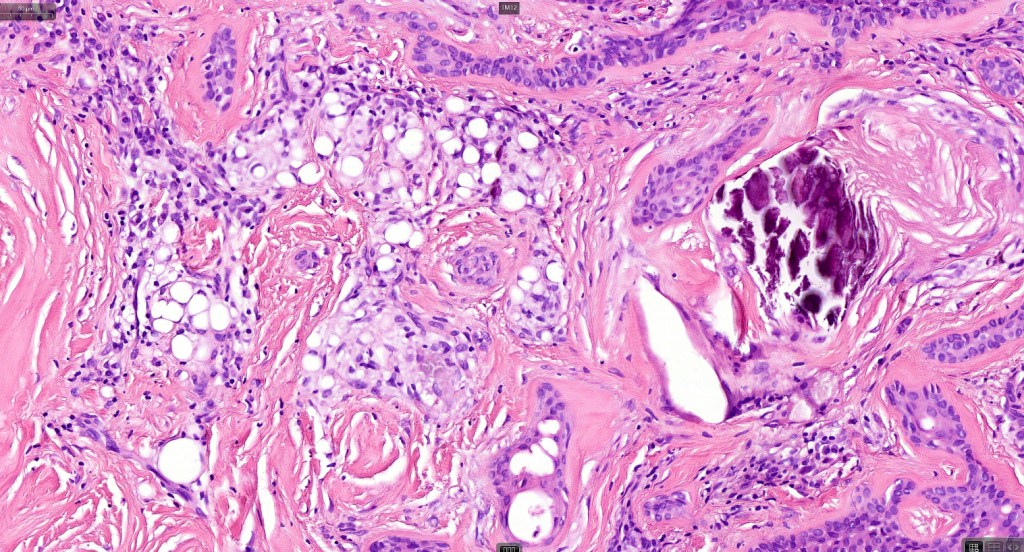

•Well circumscribed unencapsulated, nodular/multinodular silhouette composed of an admixture of epithelial & mesenchymal elements

•Clear cell change

•Mucinous metaplasia

•Plasmacytoid myoepithelial cells; clear cell change

•Follicular & sebaceous differentiation

•Myxoid change

•Fat (lipomatous mixed tumor)

•Calcification & osteoid